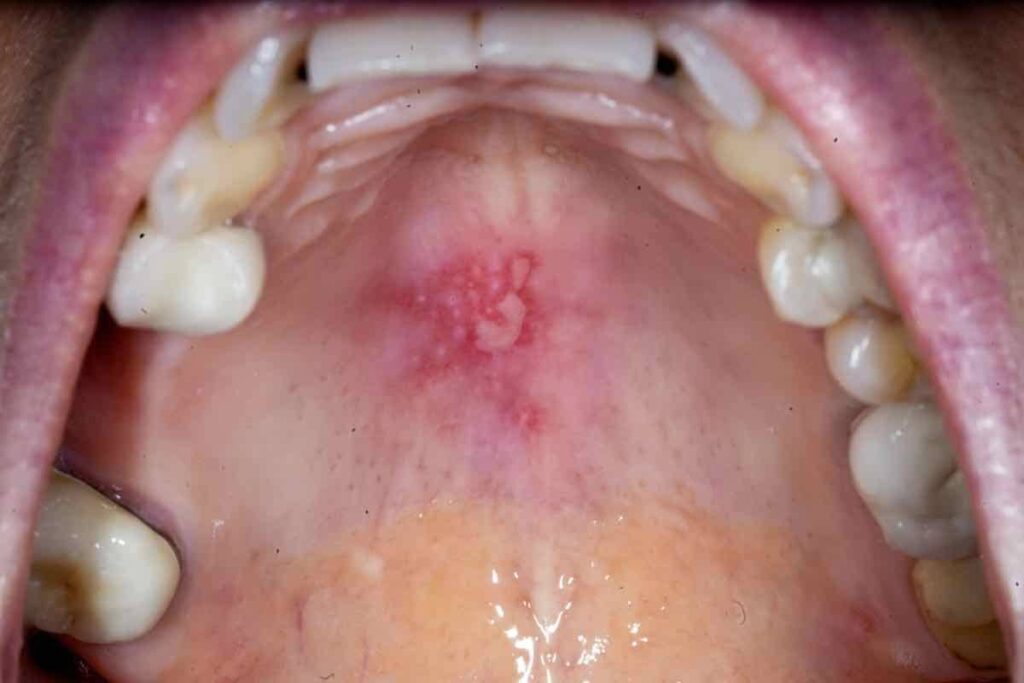

• Герпетичний стоматит: Вірусне ураження, що часто вражає слизову оболонку ротової порожнини.

1. Почервоніння та набряклість: Часто виникають унаслідок запальних процесів.

3. Наявність висипу або виразок: Це може бути ознакою інфекції або алергічної реакції.